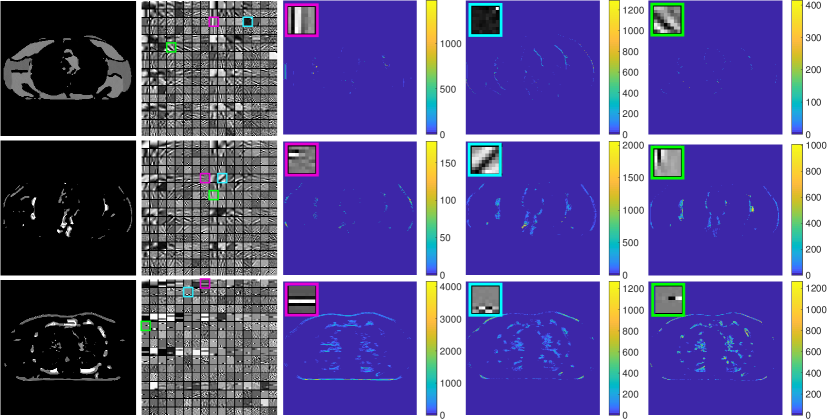

Fig. 2 (first column) shows three voxel-level classes (voxels are clustered by majority vote among patches overlapping them) for the reconstructed central axial slice. The top image only contains soft tissues, whereas the middle image shows some edges and bones in the vertical direction, and the bottom image captures some high-contrast structures. Fig. 2 (second column) shows the transforms for the corresponding classes. Each learned transform has 512 filters, and we show the first slice of 256 of these filters that show gradient-like and directional features.

Fig. 2 also shows the central axial slice of the sparse coefficient maps (volumes) for different filters of the transforms in the third, fourth and fifth columns. Each voxel value in a sparse coefficient map is obtained by applying the specific 3D filter to a 3D patch (whose front top left corner is at that voxel) and hard-thresholding the result. Coefficients for patches not belonging to the specific class are set to zero (masked out). The sparse code maps capture different types of image features (e.g., edges at different orientations or contrasts) depending on the filters and classes.